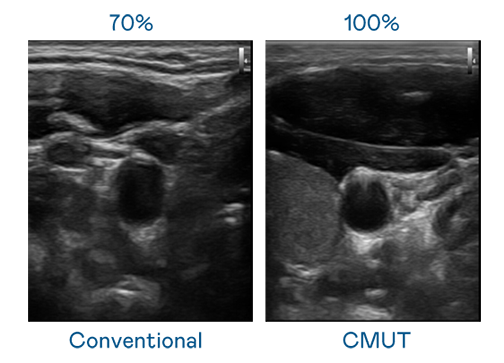

CMUT 技术是一种用电容式微机电元件来产生超音波讯号的技术。与传统 PZT 压电式技术相比,CMUT 频宽增加 30%,更宽频的超音波讯号让影像解析度大幅提升,是实现高影像品质医疗超音波扫描、促进精准医疗发展的关键技术。

大频宽带来超清晰影像

超音波影像的解析度高低,首先取决于探头能发出的讯号频宽。97国际 CMUT 可提供高清晰的超音波讯号,提供高频宽、高灵敏度、影像纹理细节更高的超音波影像,协助医护人员缩短影像判读时间及利用精准的医疗影像进行诊断。